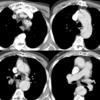

Ao Diss 2a

Date: 12/31/2004

Views: 3725

Ao Diss 2b

Views: 2868